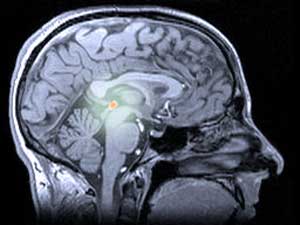

Bij mensen en andere dieren wordt melatonine geproduceerd door de pijnappelklier, een enigszins mysterieuze structuur diep in de hersenen. De pijnappelklier wordt soms het ‘derde oog’ genoemd, omdat deze bij sommige hagedissen bovenop het hoofd zit en wordt gebruikt om de schaduwen van vliegende roofdieren te detecteren.

Licht en donker zijn ook belangrijk voor de menselijke pijnappelklier en de melatonine die deze produceert. De pijnappelklier ontvangt lichtsignalen van de ogen en geeft melatonine vrij als het donker is. De melatonine werkt in op de slaapcentra van de hersenen en maakt ons slaperig. Op langere termijn reguleert de dagelijkse daling en nachtelijke stijging van melatonine ons slaap-waakpatroon, zodat dit synchroon blijft met veranderingen in daglicht.